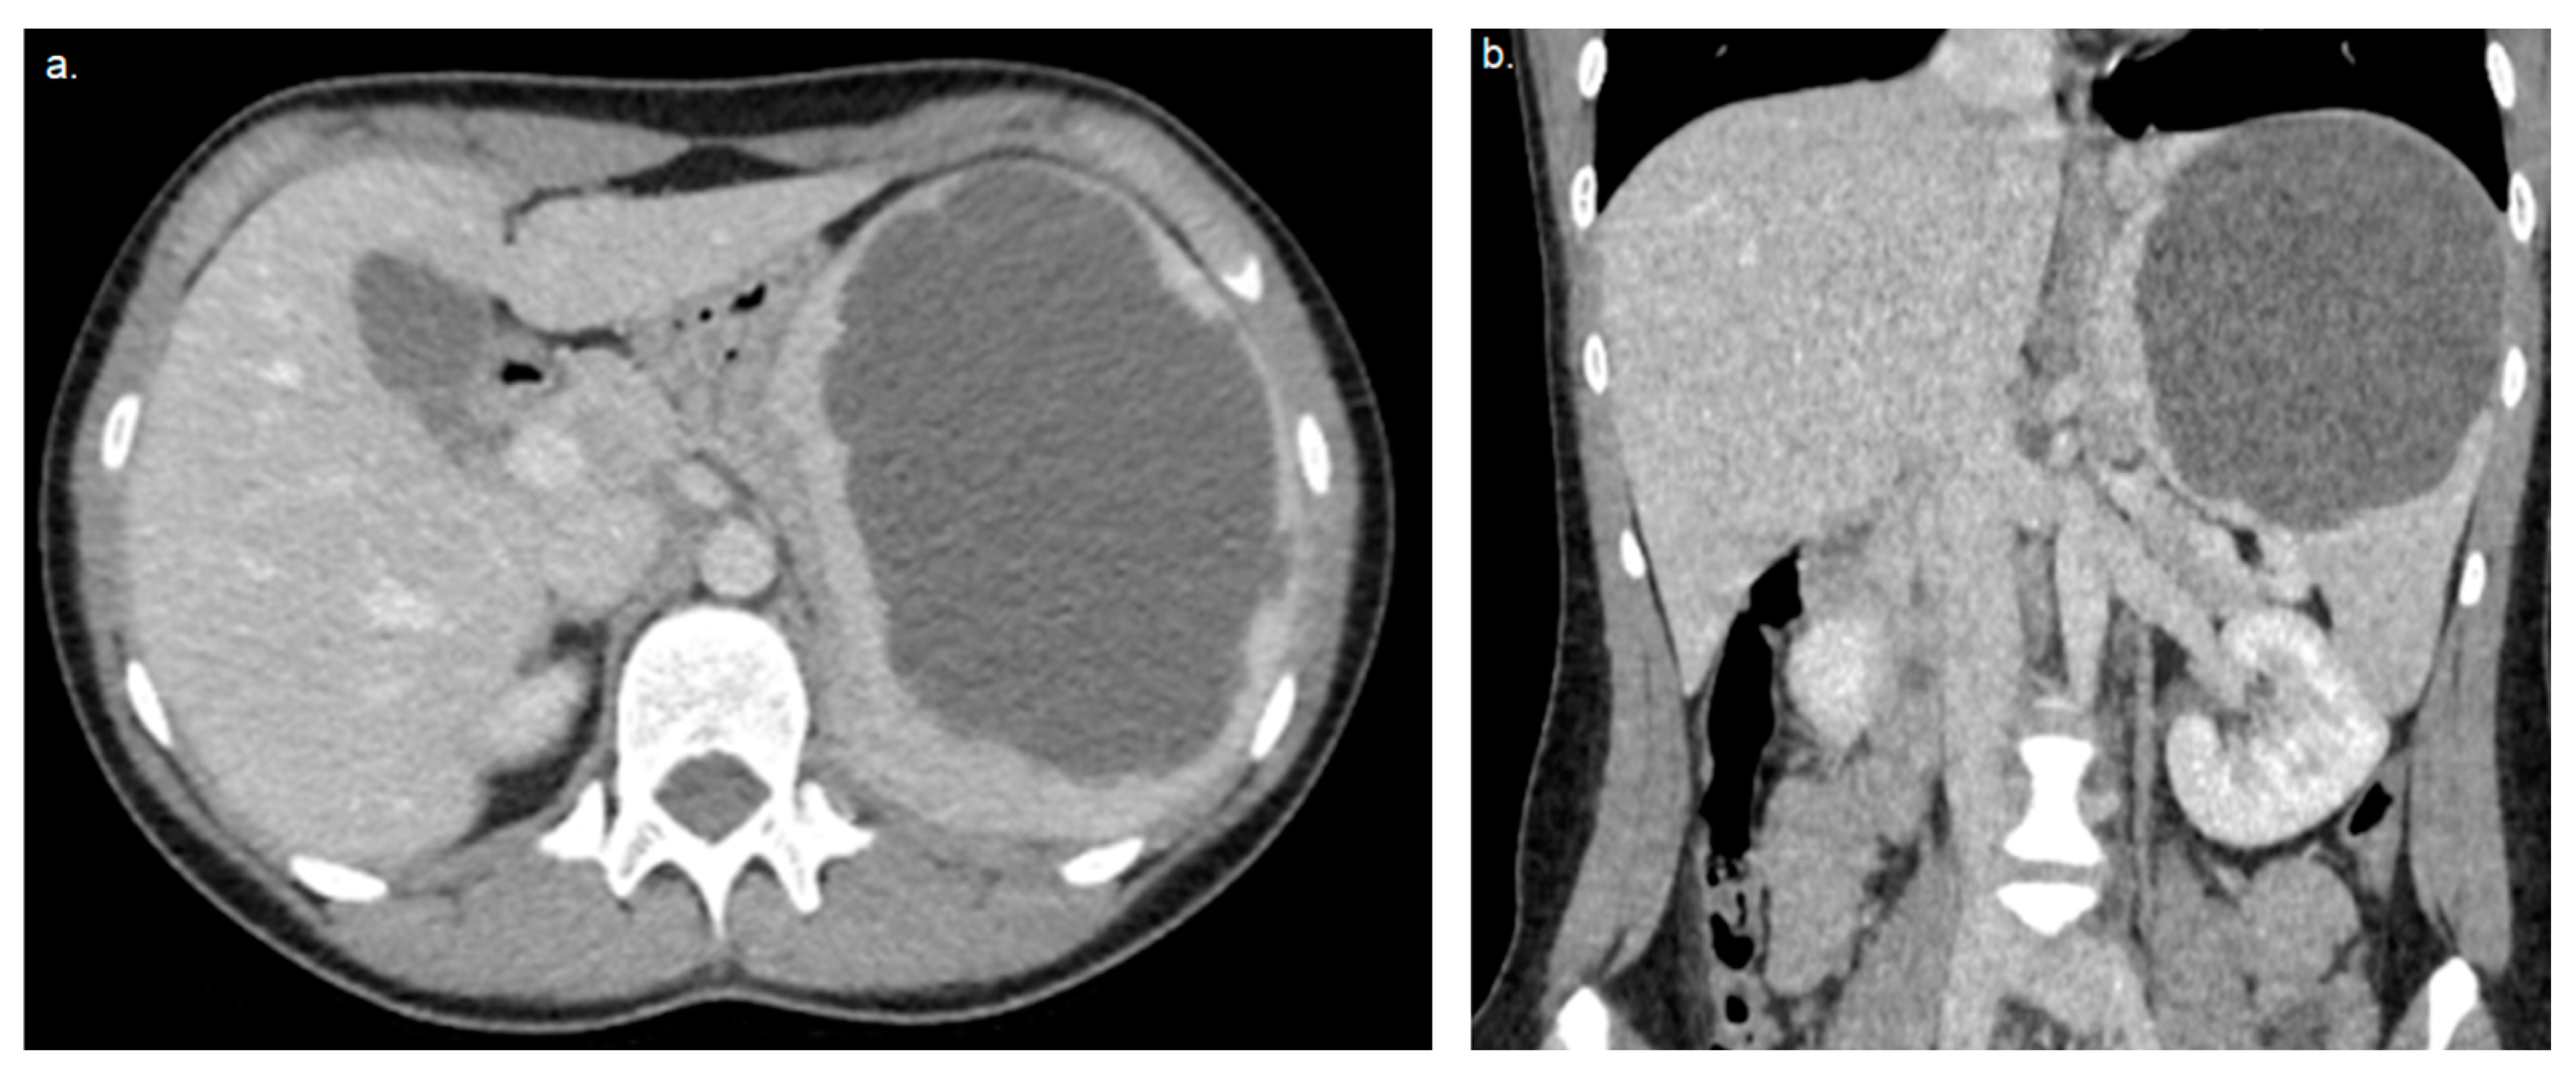

- Kofinova, D.; Rangelov, E.; Vasilevski, I.; Nansenova, V.; Bogdanova, O.; Shivachev, H. Rare case of an epidermoid spleen cyst in 15-year-old girl, XXVI National ultrasound congress in medicine, Sofia, Bulgaria, 15–17 September 2023. Diagn. Ther. Ultrasound 2023, 31, 25–26. [Google Scholar]